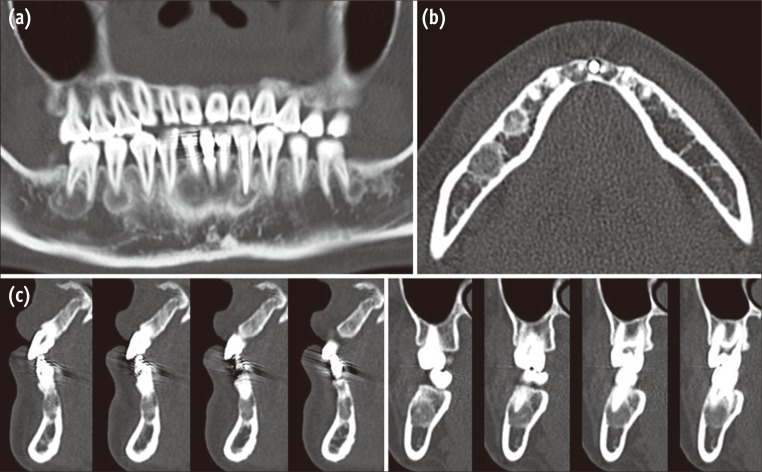

Figure 1

A series of panoramic radiographs obtained during a previous dental consultation. (a) A panoramic radiograph obtained in February, 2005 (4 years before the initial visit to our institution) when the patient's dentist initiated orthodontic treatment. Slight periapical radiolucency on #32, 33, and 42 was detected; (b) A panoramic radiograph obtained in October, 2005 when the root canal therapies were performed on #32, 33, and 42; (c) A panoramic radiograph obtained in 2007; (d) A panoramic radiograph obtained in 2008. Compared with the radiographs in 2005, the size of the lesion in the mandibular incisors increased, and a mixed radiopaque and radiolucent area was clearly distinguishable in the apical areas of the right first molar, right second molar, and left first molar.

Figure 1 A series of panoramic radiographs obtained during a previous dental consultation. (a) A panoramic radiograph obtained in February, 2005 (4 years before the initial visit to our institution) when the patient's dentist initiated orthodontic treatment. Slight periapical radiolucency on #32, 33, and 42 was detected; (b) A panoramic radiograph obtained in October, 2005 when the root canal therapies were performed on #32, 33, and 42; (c) A panoramic radiograph obtained in 2007; (d) A panoramic radiograph obtained in 2008. Compared with the radiographs in 2005, the size of the lesion in the mandibular incisors increased, and a mixed radiopaque and radiolucent area was clearly distinguishable in the apical areas of the right first molar, right second molar, and left first molar.